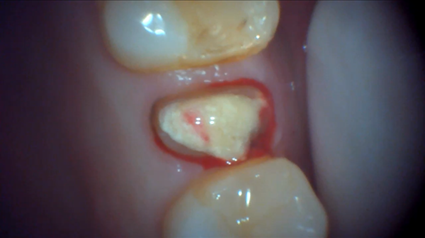

| 主訴 | 膿がたまてしまっていて痛い状態 |

| 状態 | 歯をとった瞬間に黄色い膿が吹き出た |

| 治療内容 | 根先部が破壊されてしまっていて、治療が難しい状態だったがマイクロスコープによる根管治療と、MTAセメントでの根幹充填により症状が緩和された。 骨再生因子を用いて骨を再生し、5ヶ月後には骨の再生が完了。セラミックによって審美的に補綴をして終了したケース。 |

| 料金 | 抗菌性歯内両方10万円、ファイバーコア2万円、ジルコニアクラウン12.5万円→14.5万円+税 |

※消毒費用が別途かかることがあります